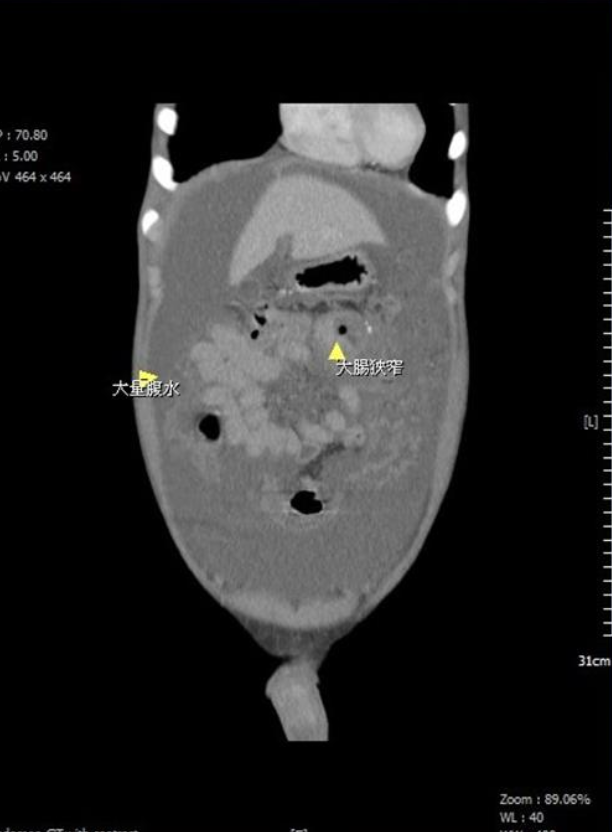

台灣苗栗一名15歲少年,近月持續腹脹不適、身體虛弱、體力下降,日前更因腹脹不適到苗栗縣大千醫院求醫,外科部主任馮啟彥經檢查發現,少年有嚴重貧血和大量腹水,抽血檢驗癌症指數CEA高達16(正常值小於5),進一步安排電腦斷層穿刺和大腸鏡切片後,證實少年罹患末期大腸癌,且癌細胞已在腹腔擴散。